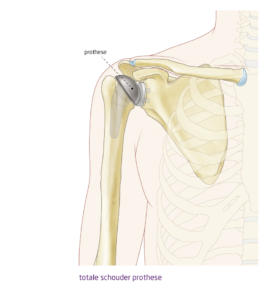

Kop-kom prothese schouder

Als je pezen van de schouder nog goed functioneren, kan je kiezen voor een kop-kom prothese. Er wordt nu een nieuwe kop en een nieuwe kom geplaatst op resp. je bovenarm en schouderblad. Je krijgt vaak weer een goede beweeglijkheid van de schouder. Als bijv. alleen de kop wordt vervangen, spreek je van een hemi-prothese.